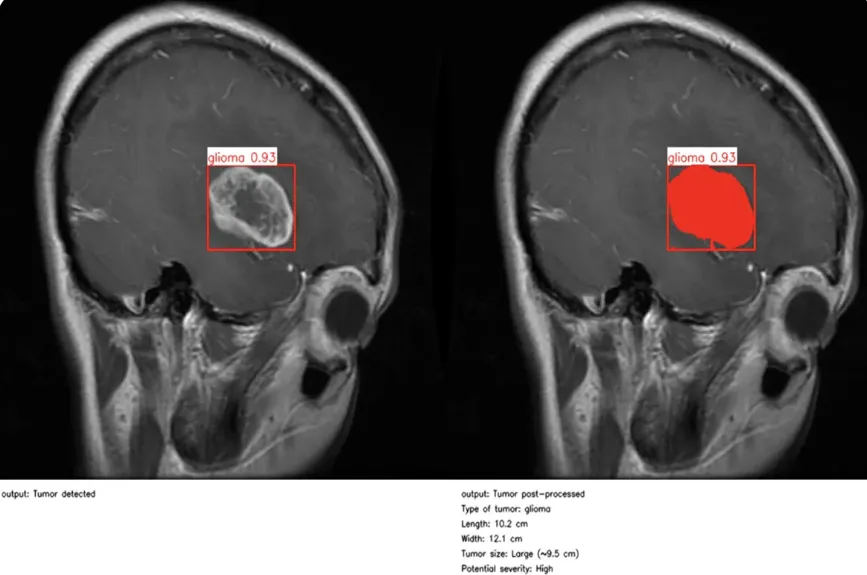

同样,随着计算机视觉成为日常临床工作流程的一部分,医疗保健领域也取得了重大进展。在医疗环境中,精确性和时间性至关重要,而计算机视觉研究和人工智能驱动的图像分析正在让临床医生做出更快、更明智的决定。

医疗保健的许多领域都是如此。以眼科为例。在英国莫菲尔德眼科医院,研究人员开发了RETFound,这是医学领域首批人工智能基础模型之一,也是眼科领域的首个人工智能基础模型。

通过自我监督学习,该模型在 160 万张视网膜图像上进行了训练,可以detect 糖尿病视网膜病变和青光眼等威胁视力的疾病,甚至可以根据细微的视网膜线索预测心力衰竭、中风和帕金森病等更广泛的全身性疾病。